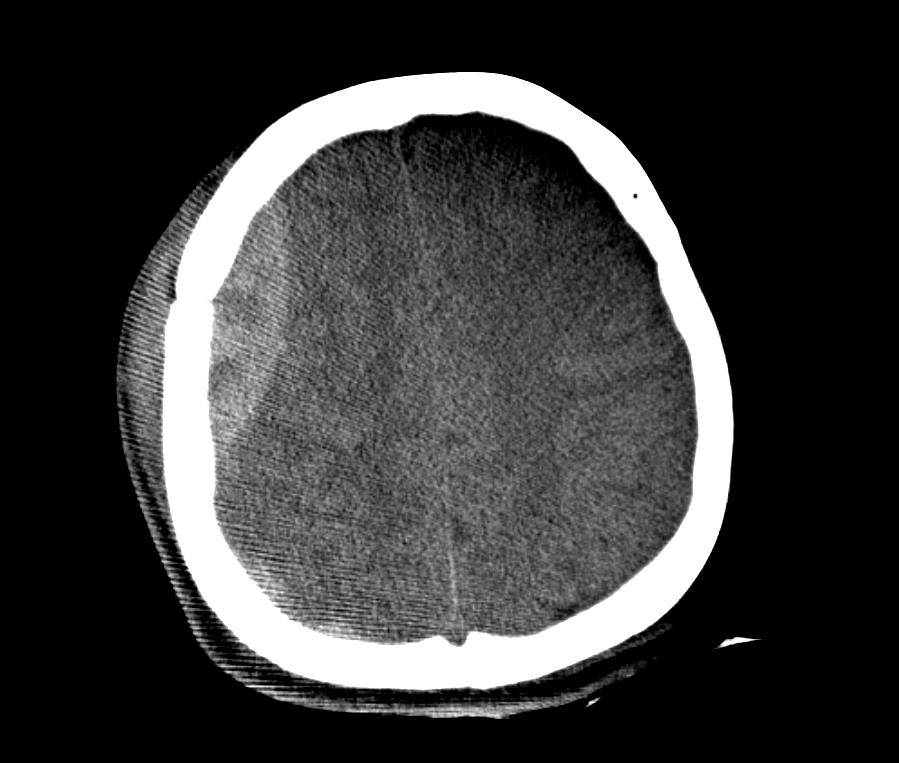

急性硬膜外血腫